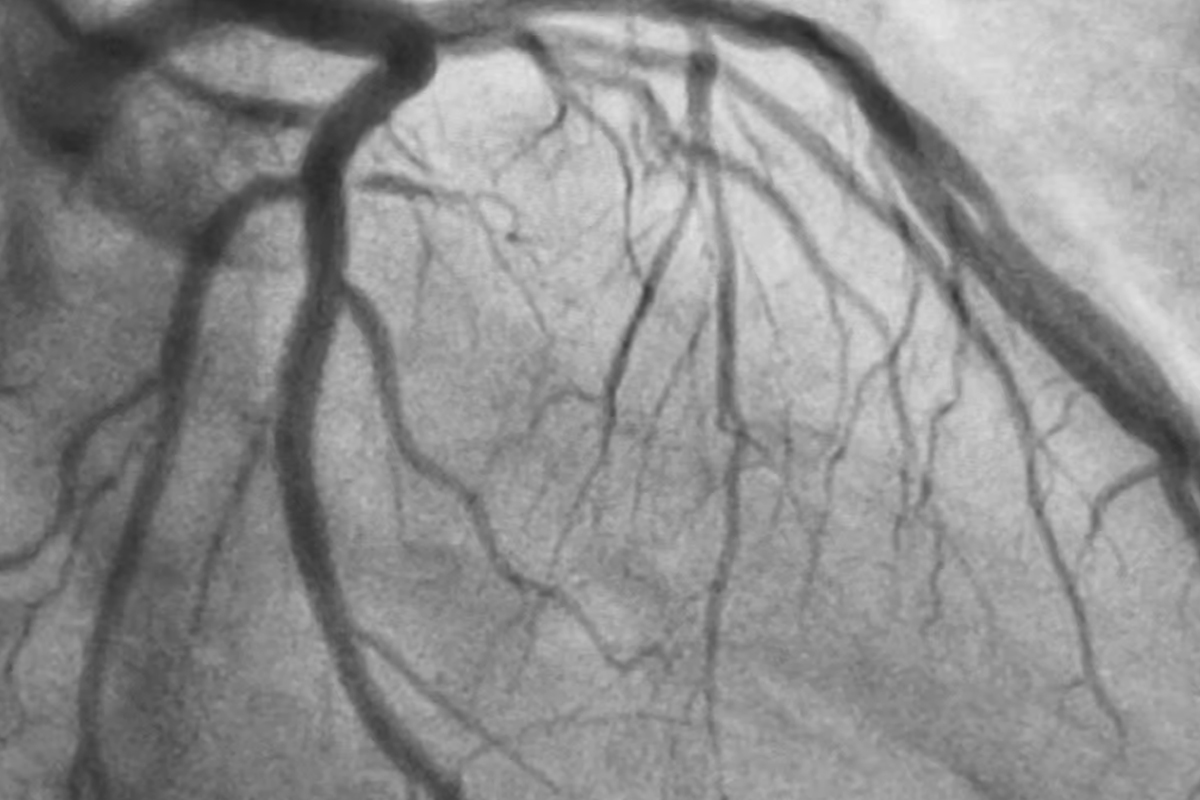

Coronary angiography is a medical procedure used to visualize the blood vessels (coronary arteries) that supply the heart with blood. It is typically performed to check for blockages or narrowing of these arteries, which can lead to conditions such as coronary artery disease, heart attacks, or angina (chest pain).

It is often done in cases of unexplained chest pain, chest pain or shortness of breathduring exertion, or a positive stress test (TMT) result.